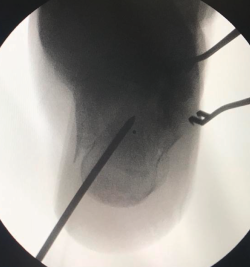

Figura 3. Varón de 59 años con fractura del calcáneo de Sanders de tipo IIA tras caída de 2 m de altura. Ángulo de Böhler precirugía de 6,3°, ángulo de Böhler poscirugía de 20,7° y a los 3 meses de 22,3°. No presentó ninguna complicación.

Cuando tenemos todos los fragmentos en su posición anatómica, habiéndose conseguido la reducción de la superficie subastragalina posterior, se fijan de manera provisional dichos fragmentos con agujas de Kirschner (aK) de 1,0 o 1,2. Estas aK fijan los fragmentos laterales de la fractura a la zona medial que normalmente está intacta. Se comprueba bajo fluoroscopio (proyección lateral) que se ha restablecido el ángulo de Böhler (Figura 3) y se fija de forma definitiva con 2 o 3 tornillos canulados de lateral a medial.